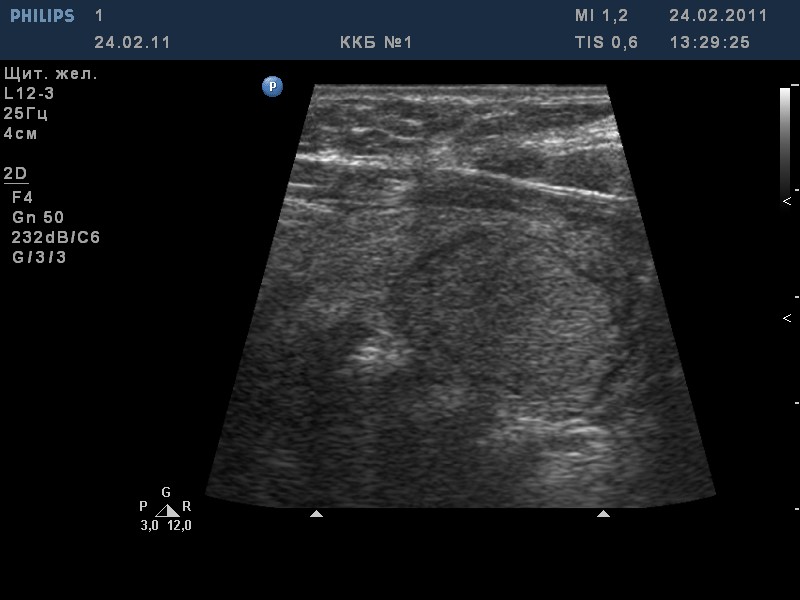

TI-RADS 4. Узлы более 1,0 см в диаметре с “малыми” признаками злокачественности для выполнения ПУНКЦИИ (рис. 3):

- солидные узлы, равномерно или неравномерно умеренно пониженной эхогенности;

- солидные узлы изо- или гиперэхогенные, имеющие “малые” признаки злокачественности:

– гипоэхогенные включения;

– округлая/шаровидная форма;

– неравномерно утолщенное хало;

– макрокальцинаты.

Рис. 3. TI-RADS 4: а – узел шаровидной формы, с ровными и четкими контурами, умеренно пониженной эхогенности, с участками более низкого эхо, с макрокальцинатом. Узел окружен тонким хало (фолликулярная неоплазия); б, в, г (поперечное и продольное сканирование левой доли ЩЖ) – изоэхогенные узлы с гипоэхогенными включениями, с четкими контурами, с тонким хало (фолликулярная аденома); д – изоэхогенный узел с гипоэхогенными включениями, с неравномерно утолщенным хало (фолликулярный рак).